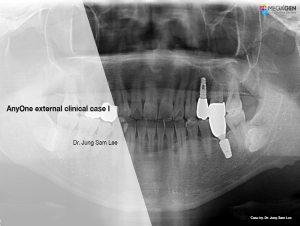

AnyRidge,Dr. Miguel Stanley,Immediate loading,Maxillary Anterior,Scientific background,Single replacement